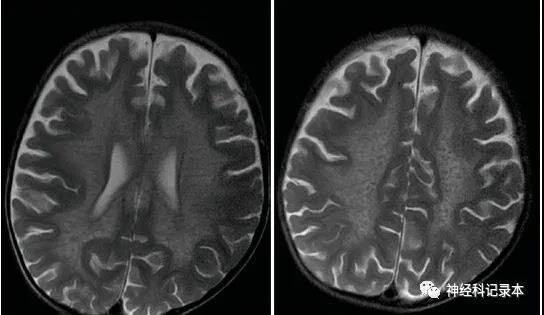

1例3岁患儿的影像资料如下:

T2WI:左图“虎斑”征,右图“豹皮”征。